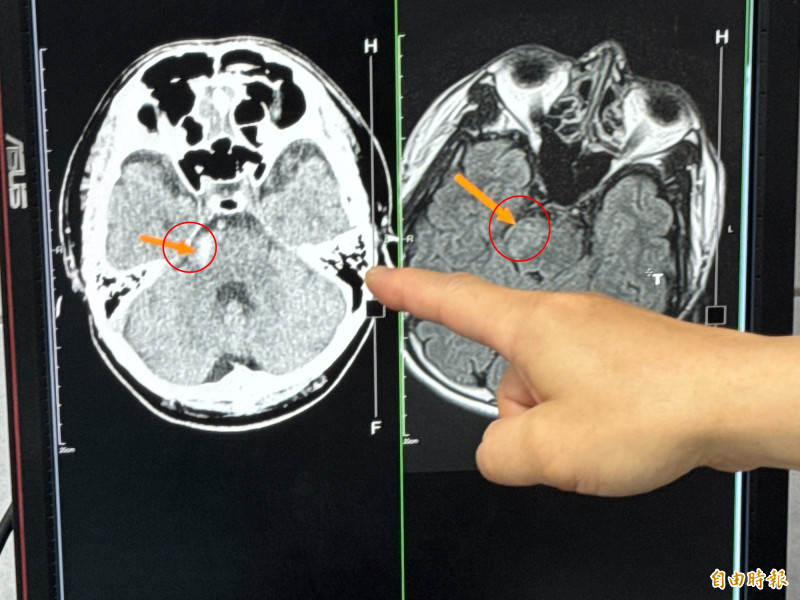

〔記者張軒哲/台中報導〕台中市一名40多歲男子,日前開車上班途中,突然感到身體不適,手腳逐漸麻木沒力氣,馬上停車自行叫救護車,送到大甲李綜合醫院急診室時,經過檢查發現竟是腦幹出血,醫師說,腦幹出血致死率極高,但患者非常幸運,搶在黃金期救治,逐漸康復後還能行動自如,是很罕見的個案。

大甲李綜合醫院副院長、神經外科主治醫師李偉裕表示,患者開車開到一半,自述突然肢體無力、頭痛、頭暈、冒冷汗,送到急診室時意識還清楚,檢查後發現是腦幹出血,馬上轉入加護病房,由於出血量不多,先針對血壓、腦水腫、腦壓進行藥物控制與治療,避免後續可能有腦血管再爆裂。

「腦幹出血10位患者有9位會致死,剩下一位恐就是植物人或重殘癱瘓。」李偉裕說,該患者住加護病房期間,擔心恐怕會有「腦血管未爆彈」,用核磁共振血管攝影進一步檢查,還好沒有發現有其他的動脈瘤,不過,因為腦幹出血幾乎沒有事前徵兆,因此,建議患者在出院後應該要定期追蹤檢查,也要避免自己給自己的壓力過大,更要注意控制血壓。